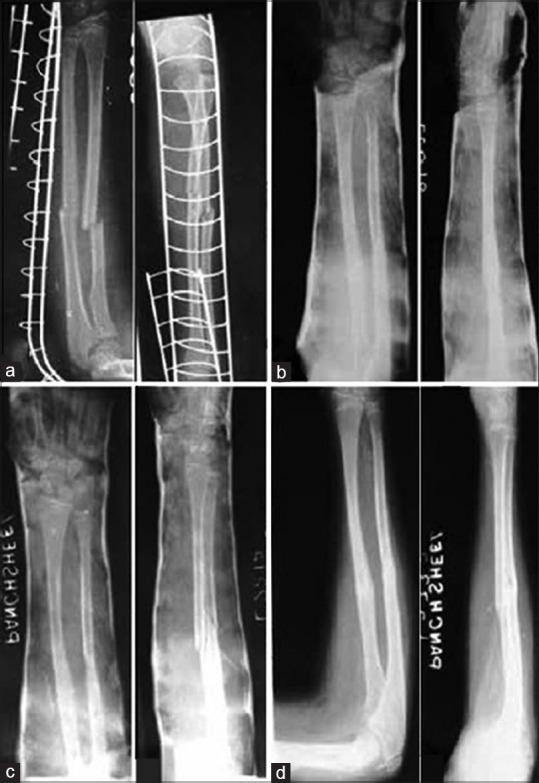

113 patients of age range 2-13 years with displaced forearm fractures, treated by closed reduction and cast were included in this prospective study. Prereduction and postreduction angulation, translation, and shortening were noted. In addition, for distal metaphyseal fractures, obliquity angle was noted. In postreduction X-ray, apart from fracture variables, casting indices were also noted (cast index [CI] for all patients with three-point index [TPI] and second metacarpal radius angle in addition for distal metaphyseal fractures). In 2 week, X-rays were again obtained to check for significant redisplacement. These patients were managed with remanipulation and casting or were operated if remanipulation failed. Comparison of various risk factors was made between patients with significant redisplacement and those which were acceptably reduced. A subgroup analysis of patients with distal metaphyseal fractures was done.

Thirteen (11.5%) patients had significant redisplacement; all of them required remanipulation. No association with respect to age, sex, level of fracture, side of injury, surgeon's experience, number of bones fractured, and injury to definitive cast interval was seen. The presence of complete displacement in any of the plane in either of the bones was seen to be highly significant predictor of redisplacement ( < 0.001). Postreduction angulation more than 10° in any plane in either of the bone and fracture obliquity angle in distal metaphyseal fracture also had a highly significant association with redisplacement. There was a significant difference in the mean values of all three casting indices assessed. TPI was the most sensitive casting index (87.5%).